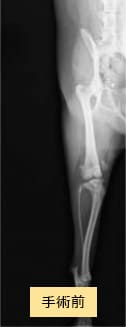

パピヨン×マルチーズ(10ヶ月齢、雌)グレードV 外科手術

- 【初診時症状】

- お散歩時跛行し、以降頻繁に外れるようになった

- 【手術】

- 脛骨粗面転位術、関節包縫縮を実施

- 【経過】

- 同居犬がおり、安静の維持が難しいため、術後2週間入院。術後4週間で屋内での運動制限を徐々に解除、8週間でお散歩の距離を少しずつ伸ばしていくも歩行問題なし。術後しばらくは右後肢の術創を気にして舐めていたが経過観察期間に徐々に消失。現在は制限なく生活。